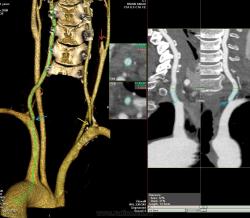

Наблюдение Nela.

Мужчина, 62 года. Перенес ишемический инсульт в бассейне правой средней мозговой артерии.

На КТ-ангиографии выявлена окклюзия правой внутренней сонной артерии в области развилки в виде паламени свечи (красная стрелка), стеноз высокой степени в устье правой вертебральной артерии (желтая стрелка), небольшой перегиб в устье левой вертебральной артерии (голубая стрелка).